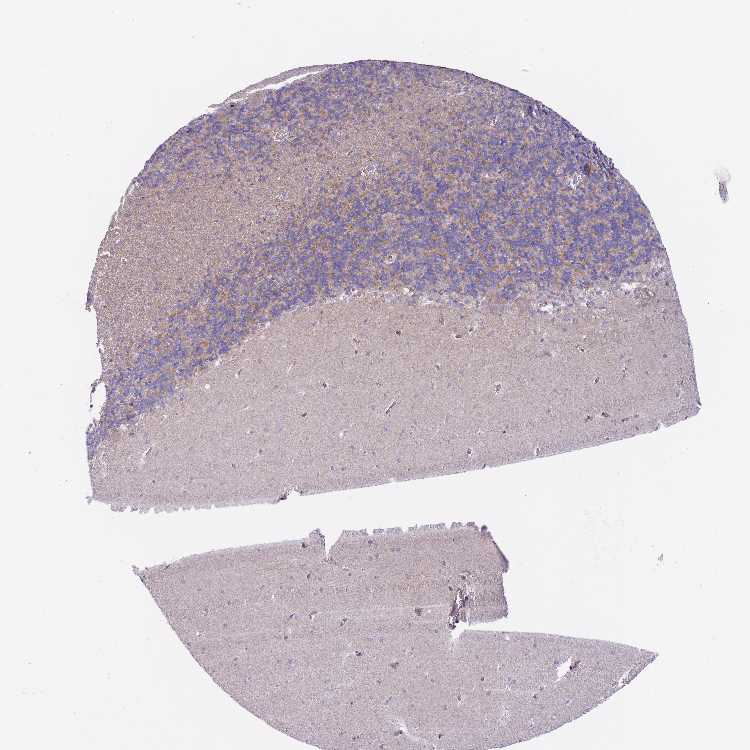

BRAIN CEREBELLUM Show tissue menu

CEREBELLUM - Expression summary

Protein expression

Cerebellumi

On the top, protein expression in current human tissue, based on all annotated cell types, is reported with the units not detected (n), low (l), medium (m) and high (h). Underneath, protein expression in each annotated cell type are reported using the same units.

Protein expression data is based on knowledge-based annotation. For genes where more than one antibody has been used, a collective score is set.

If knowledge-based annotation could not be performed for a gene, no data is displayed here. View antibody staining data further down this page.

Cells in granular layer: Medium

Cells in molecular layer: Low

Purkinje cells: High

CEREBELLUM - Antibody stainingi

Antibody staining in the annotated cell types in the current human tissue is reported as not detected, low, medium, or high, based on conventional immunohistochemistry profiling in selected tissues. This score is based on the combination of the staining intensity and fraction of stained cells.

Each image is clickable and will lead to virtual microscopy that enables deeper exploration of all samples and also displays staining intensity scores, fraction scores and subcellular localization as well as patient and tissue information for each sample.

Antibody HPA042708Antibody HPA043505

Purkinje cells HighNot detected

Cells in granular layer MediumMedium

Cells in molecular layer LowNot detected